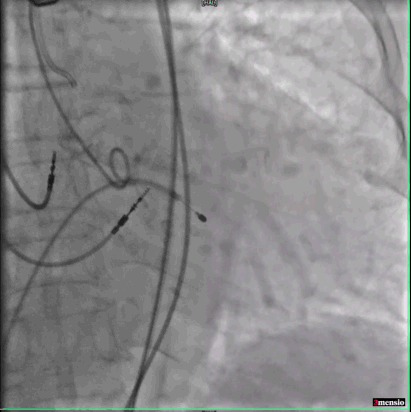

主动脉根部造影